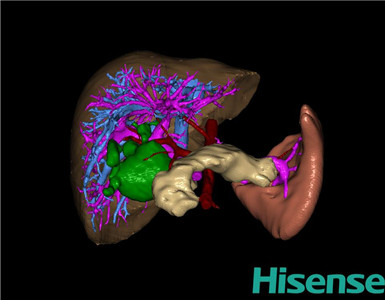

将0.625mm双源薄层CT资料的静脉期和动脉期Dicom格式文件导入海信CAS系统。

通过调节窗宽窗位调整CT序号,对肝实质,胆囊,下腔静脉,肿瘤,肝动脉、门静脉及肝静脉等进行三维重建;系统自动计算肝脏体积。

术前三维重建:

重建图片